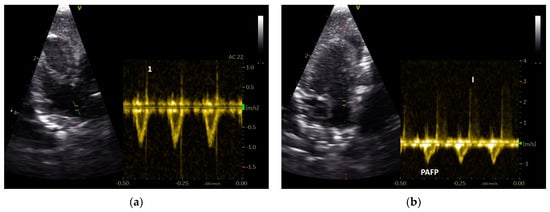

Figure 4.

PW Doppler sonographic blood flow profiles of the aorta (a) and pulmonary arteries (b–d) of Congo grey parrots without sonographic evidence of heart disease (GPs from group 1). The acceleration phase of the blood flow is visible in red and the deceleration phase in blue in (a,b). A sample gate is placed in the area of the aortic (a) or pulmonary valve (b–d); AC: angle correction. The colour scale on the right side of the images is calibrated in m s−1.

3.1. Shape of PAFP and AOFP of Grey Parrots

Our examinations of the systolic Doppler flow profiles of the GPs revealed a significant difference between the shape of their PAFP and AOFP. The percentage of the AT in the total ET of the AOFP and PAFP, as a reflection of the blood flow profile’s shape, indicated that the acceleration phase of the blood flow of the PA was significantly longer, while the deceleration phase of the PAFP was significantly shorter compared to the AOFP (p < 0.001; Mann–Whitney U test) in the examined GPs (Figure 4). The PAFP exhibited a rounded shape with an AP that was slightly shorter than the DP (p < 0.05; Mann–Whitney U test) in the examined GPs that did not display any sonographic evidence of heart disease (group 1; Table 6). The AOFP was defined by a short AP and a longer DP (p = 0.005; Mann–Whitney U test; group 1; Table 5; Figure 4).